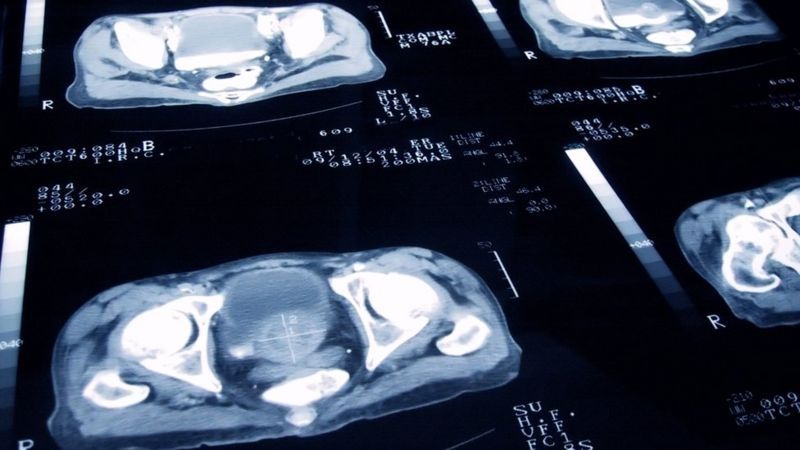

La resonancia magnética proporciona imágenes detalladas de las estructuras corporales.

A diferencia de los rayos X y la tomografía computarizada, no depende de la radiación ionizante (que está relacionada con un mayor riesgo de cáncer) y se cree que es segura.

Es buena para detectar el cáncer de próstata temprano y para la "vigilancia" (monitoreo de la enfermedad).

Pero las resonancias magnéticas son costosas y las máquinas son voluminosas, consumen mucha energía y generalmente están confinadas a los hospitales. Esto limita su uso.